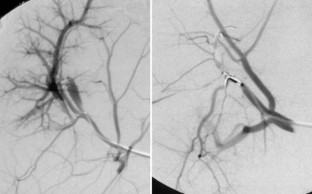

Im interdisziplinären Konsens wurden 182 Patienten (Lebertumoren: 131, andere Tumoren—Knochen, Lunge, weitere Tumoren: 51) mit 1–6 Applikatoren behandelt. Die Interventionen erfolgten in Kombination verschiedener Modalitäten (CT/MRT; CT/US) oder ausschließlich im geschlossenen MRT (1,5 T) mit direkt postinterventioneller MRT-Kontrolle.

Laser ablation was performed in 182 patients (liver tumors: 131, non hepatic tumors—bone, lung, others: 51) after interdisciplinary consensus was obtained. The procedure was done using a combination of imaging modalities (CT/MRI, CT/US) or only closed high field MRI (1.5 T). All patients received an MRI-scan immediately after laser ablation.

The treatment of tumors of the liver and other organs up to 5 cm by laser ablation was a safe procedure with a low rate of complications and side effects. Image guidance by MRI is advantageous for precise tumor visualization in all dimensions, therapy monitoring, and control of laser ablation results.

Abb. 7

Abb. 8